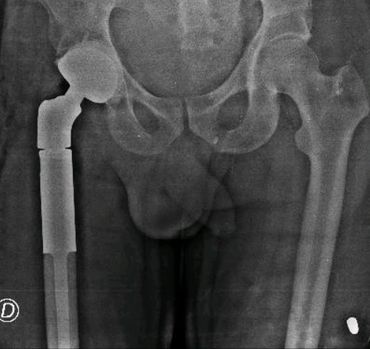

Reemplazo total de cadera no convencional por inflitración tumoral del tercio proximal del femur